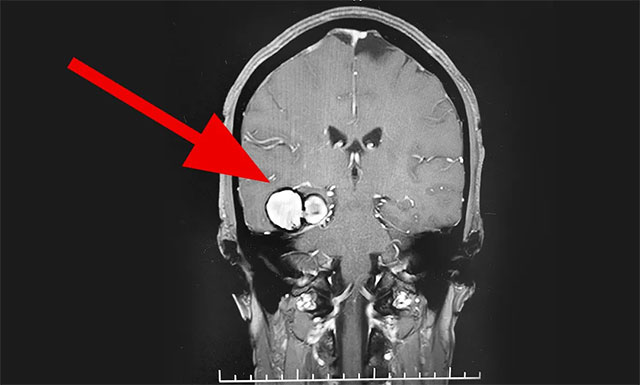

入院后,行MR頭顱MRI平掃+增強+DWI+MRA顯示,右側(cè)顳葉見一團(tuán)塊狀異常信號影,大小為 2.2cm×3.6cm×3.5cm, T1WI 呈高信號為主、邊緣低信號環(huán)繞,T2WI、FLAIR及DWI高、低混雜信號、周邊環(huán)狀低信號,病周未見明顯水腫帶;增強后病灶未見明顯強化征象?紤]患者有反復(fù)出血表現(xiàn),為鑒別診斷,行全腦血管造影術(shù)示大動脈硬化,內(nèi)膜毛糙,余血管未見明顯異常。

▲ MR顯示“血管瘤”位于右側(cè)顳葉

綜合患者癥狀、相關(guān)檢查,由潘仁龍主任、李士其教授、吳治群博士組成的專家團(tuán)隊會診后考慮,可能性較大的是顱內(nèi)海綿狀血管瘤。患者已經(jīng)明確有反復(fù)出血史,手術(shù)指征明顯,需行手術(shù)切除治療,預(yù)防再次出血引起神經(jīng)功能及癲癇等癥狀。